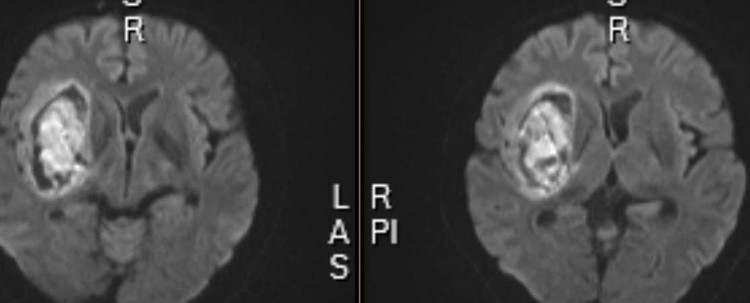

| Hình ảnh phim chụp người bị xuất huyết não. Ảnh TTYT huyện Thanh Thủy |